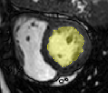

4.3.2 Analysing Heart Function in 4D MRI

Four-dimensional imaging of patient anatomy is gaining interest in the medical community. The temporal analysis of anatomical structures is used to extract the characteristics of related dynamic processes, which often indicate certain pathologies [16, 26, 3]. In this section, we apply nWESD to the shapes of the hearts extracted from four dimensional cardiac images of five different patients. The scan of each patient captures a full cycle of one heartbeat as a series of 20 3D images. Each image shows the left ventricle (LV) at a specific point in the cycle, from which we manually segment the corresponding blood pool. Our reference is the blood pool extracted from the first frame (diastole). We compute the nWESD scores between this reference and all other shapes extracted from the series of images. Here, we do not normalise the eigenvalues with respect to the global scale since size change is an important aspect of the heartbeat dynamics. The graph given in Figure 8 shows the results of these measurements over time across the five patients. The figure also shows some exemplary images and shapes. We observe that the symmetry of the heartbeat along the systolic (as the blood pumps out of the LV pool) and the diastolic phases (as the blood fills in the pool) is well captured with the nWESD score. Furthermore, the end-systolic phase (the time point with the largest distance w.r.t. the reference) is at different time points for different patients, which is to be expected since the different patient scans are not synchronized in time. In summary, WESD well captures the dynamics of the beating heart, which is to be expected given the continuous link between the differences in eigenvalues and the difference in shape (see Section 2).